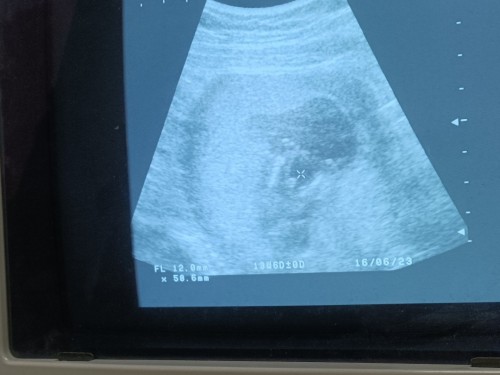

14week แม่ๆรู้เพศกันยังคะ

คุณหมอบอก 60-70% ผมเป็นผู้ชายแน่ๆ ♥️🥰

ของเรา ซาวน์ตอน 14 week เหมือนกันค่ะ แต่หมอบอกผู้ชาย 100%เลยค่ะ เพศเห็นชัดมาก หมอว่าซื้อผ้าตั้งใว้ได้เลย😊 แต่ตอนนี้ 15 Week แล้วค่ะ